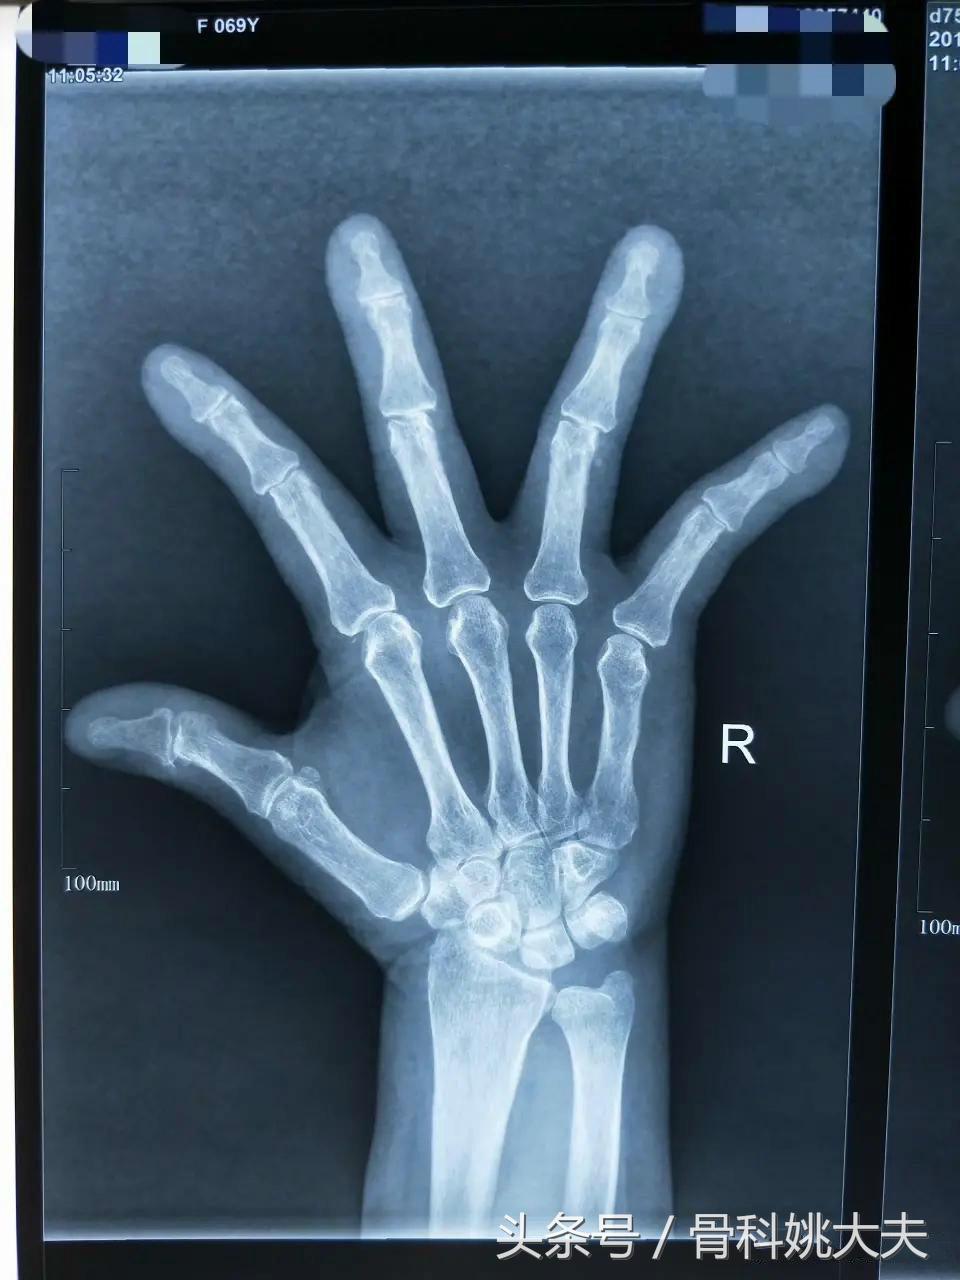

神奇的一双手,75岁的赵嗲嗲来医院看病,手指关节变形疼痛的厉害,在好多家医院都看过了,都怀疑是风湿性关节炎,可是抽血检查又没有问题…

6. 手的X线照相具有典型的类风湿关节改变者(包括糜烂和骨质脱钙)。